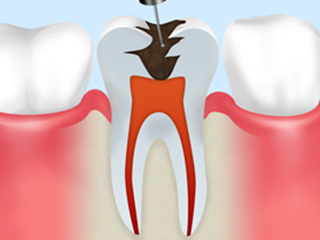

根管治療の流れ

step1

虫歯菌に冒されている部分をすべて削り取ります。